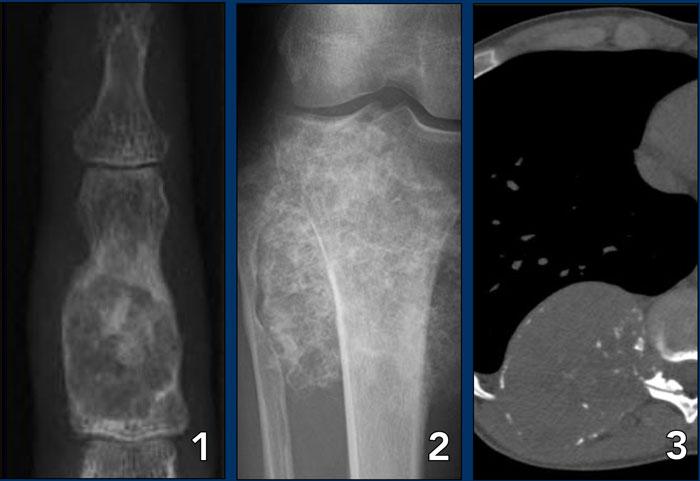

Ewing’s sarcoma with permeative growth through the haversian channels accompanied by a large soft tissue mass

Phá hủy vỏ xương (3)

Trong nhóm u ác tính tế bào tròn nhỏ bao gồm sarcoma Ewing, u lympho xương và sarcoma xương tế bào nhỏ, vỏ xương có thể trông gần như bình thường trên X-quang, trong khi khối u phát triển thấm nhuận qua các ống Havers.

Những khối u này có thể đi kèm với một khối mô mềm lớn trong khi hầu như không có dấu hiệu phá hủy xương nào có thể nhìn thấy được.

Images

- Sarcôm Ewing

Phim X-quang không cho thấy bất kỳ dấu hiệu nào của sự phá hủy vỏ xương. - MRI cho thấy khối u lớn trong xương và sự phát triển thấm nhiễm qua các ống Havers kèm theo một khối mô mềm lớn, hầu như không nhìn thấy trên X-quang.